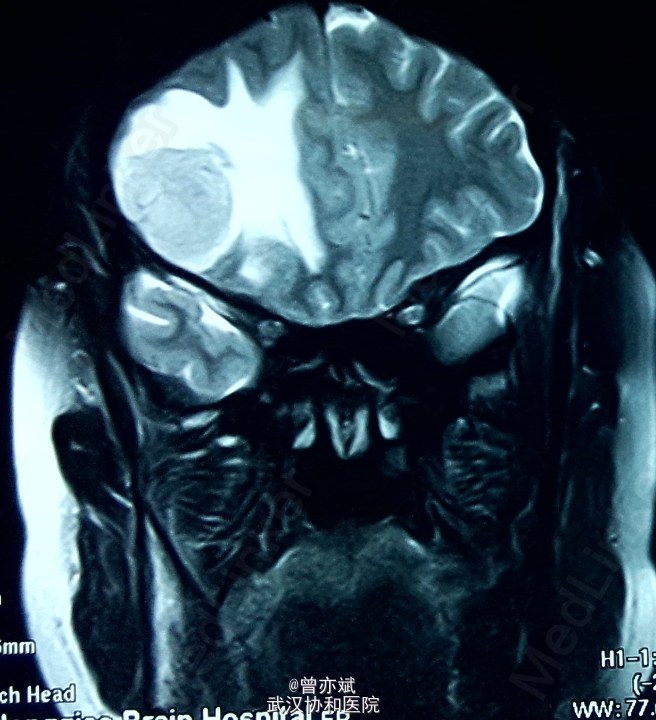

蝶骨嵴 or 大脑凸面脑膜瘤?

患者女,48岁,因“头晕1年”入院。近来出现左侧肢体肌力下降。

查体除左侧肢体肌力稍差4+,余无阳性体征。MRI如下